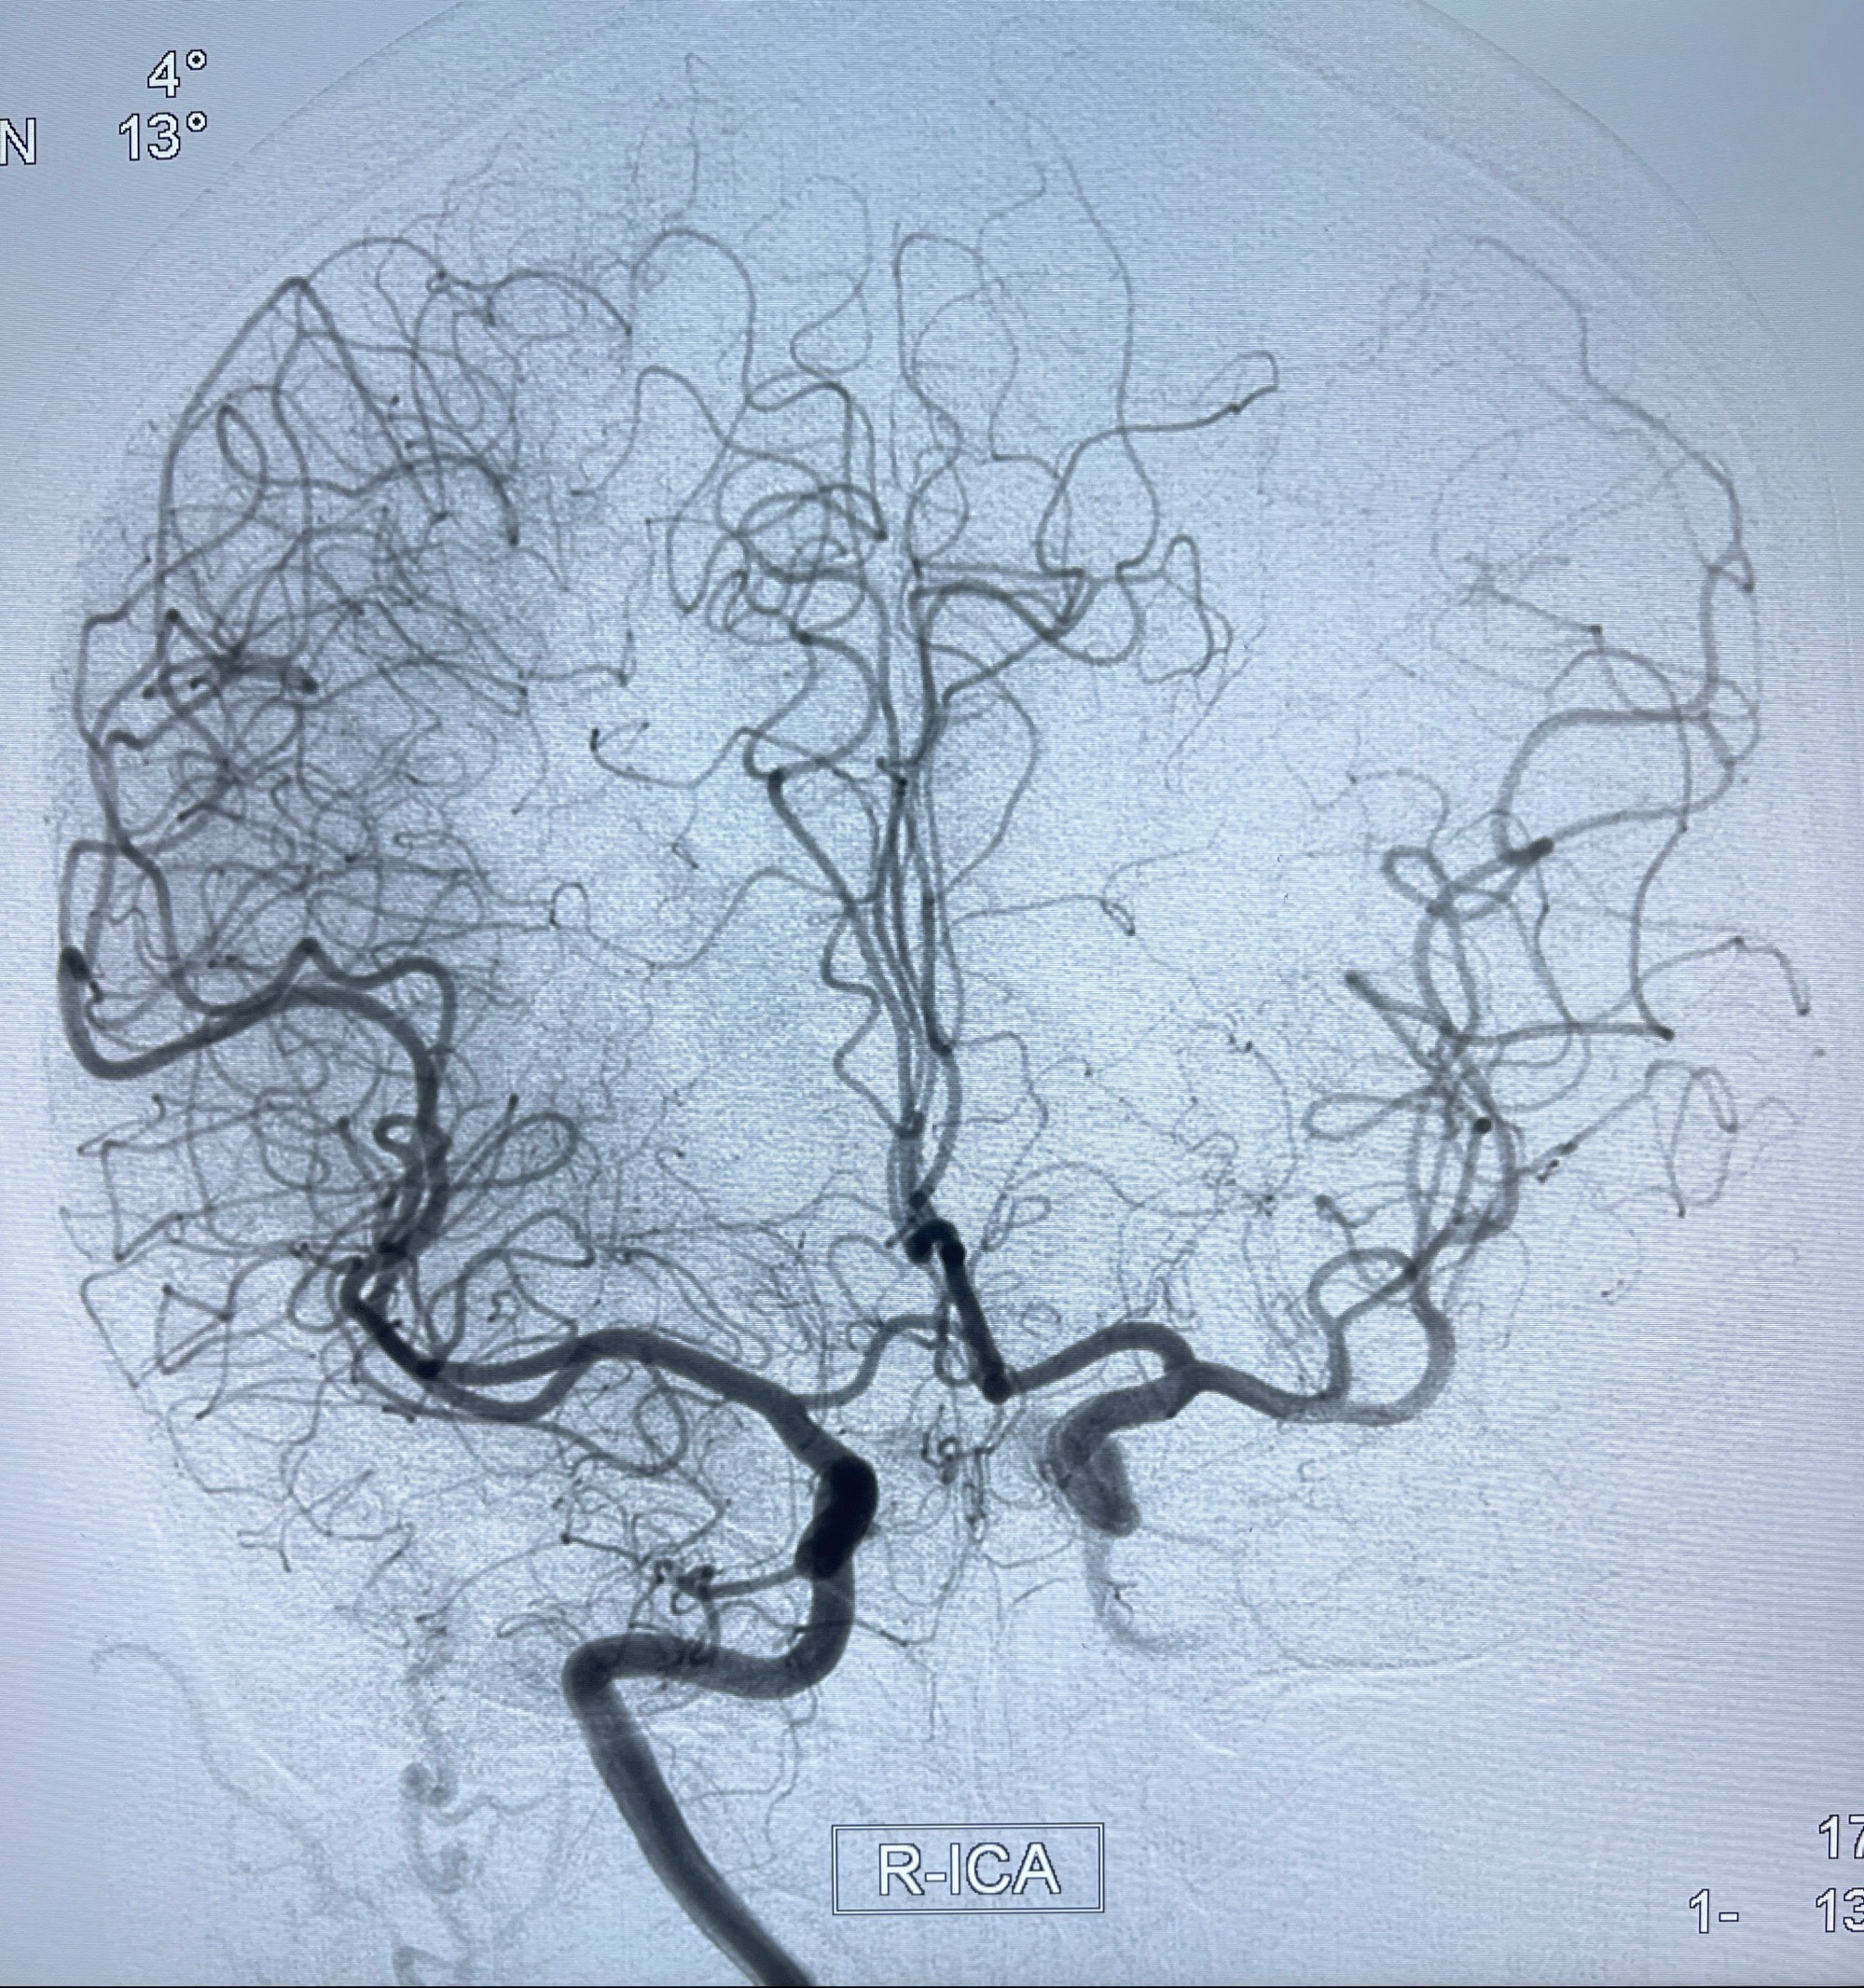

2023-08-30DSA:左侧颈内动脉眼动脉动脉瘤,约3*9.2*7.3mm大小